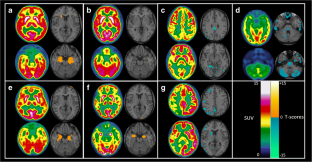

Fig. 2